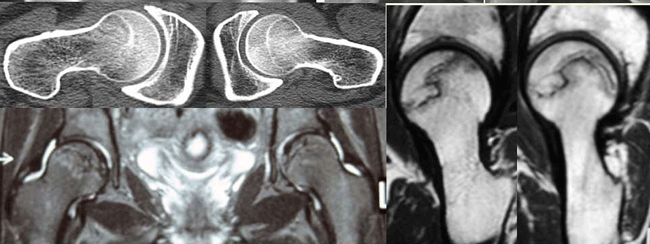

Ⅲ期早中期臨床癥狀:由于股骨頭供血不足,導致骨內壓增高,刺激股骨頭軟骨和滑膜引起疼痛,X片示股骨頭輪廓中斷、有半月征,塌陷大于2mm,關(guān)節表面凹凸不平,有死骨形成,股骨頭變扁,關(guān)節間隙正常?!夺t生在線(xiàn)問(wèn)診,上傳檢查報告單或X片給醫生查看

Ⅲ期晚期臨床癥狀:股骨頭內骨小梁明顯變形或消失、股骨頭內有大小不等囊狀破壞區、周?chē)不錾?、股骨頭持重面塌陷、骨質(zhì)碎裂變形。關(guān)節囊炎性變明顯可伴有關(guān)節積液。

晚期臨床癥狀:疼痛固定在腰骶、髖、腹股溝、大腿內側及膝關(guān)節處,持續性疼痛極難緩解。關(guān)節活動(dòng)受限,跛行明顯,嚴重者行走困難,或喪失勞動(dòng)能力,患肢明顯肌肉萎縮,關(guān)節腫脹、交鎖、彈響。